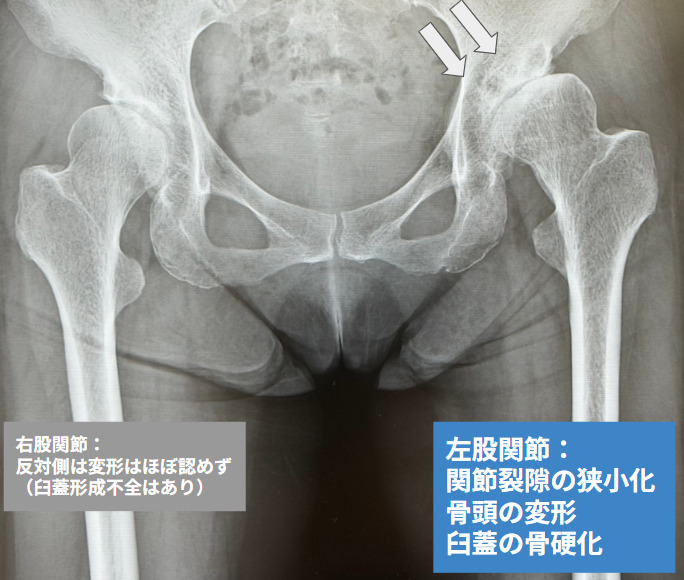

寛骨臼形成不全はレントゲンで診断が可能です。レントゲンの両股関節正面像において CE角が20°以下のものを寛骨臼形成不全、もしくはSharp角が成人男性で38〜42°以上、成人女性で43〜45°以上のものを寛骨臼形成不全と診断します。